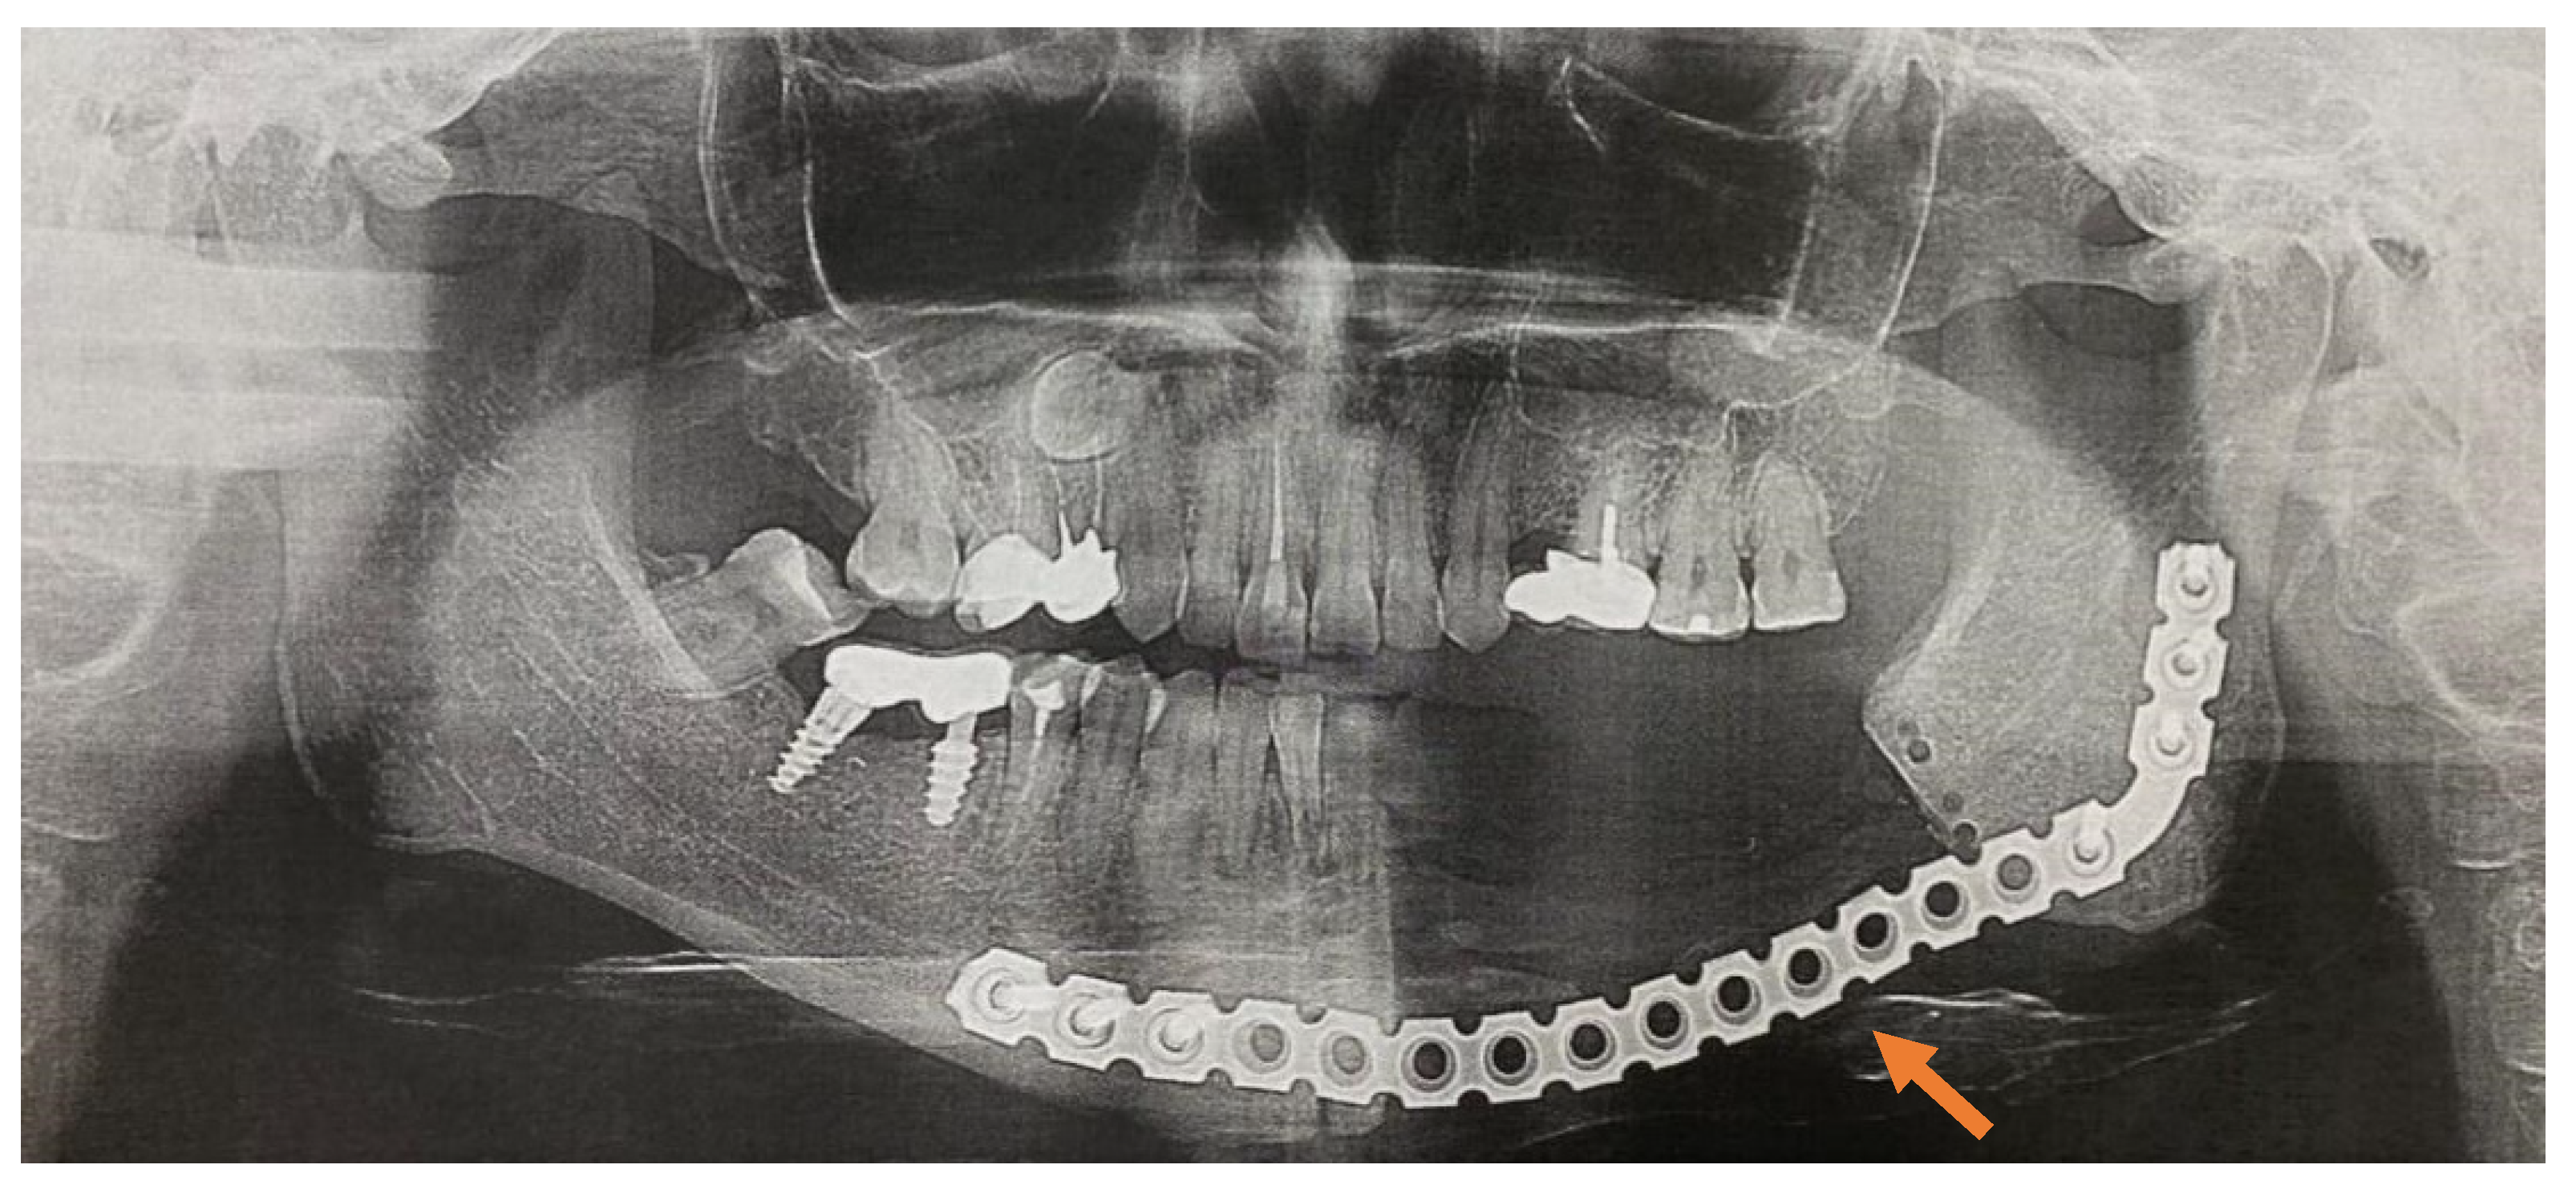

An analysis of the results obtained from the Numeric Pain Rating Scale demonstrated that the mean pain intensity before treatment was 8.9 points in the control group, and 9.7 in the main group (Figure 4). These values are indicative of “unbearable pain.” After treatment (30 days), the pain score in the control group decreased and amounted to 4.1; this is evidence of the persistence of “moderate pain” in the patients. In patients who underwent segmental jaw resection (Figure 5a,b and Figure 6), the mean pain intensity was 0.5. There was no relationship with gender, but there was a direct relationship between the intensity of the pain and the stage of the process (CI = 95%).

Table 3 presents the results obtained with the Visual Analog Scale in patients with MRONJ after six months, which make it possible to assess changes in this parameter over time. After treatment, this parameter value was 3.6 in the control group and 0.1 in the main group (Figure 7a–d).

In the patients in the main and control groups, the pain intensity index values before treatment approached similar values. After surgery, the pain intensity index in the main group was close to normal values. In the control group, 30 days after conservative treatment, there was a tendency for the parameter to decrease; however, after six months, it did not reach the “no pain” mark (Figure 8 and Figure 9a,b).

Figure 1. (ad) Patient A: 47-year-old female. DS: Medication-related osteonecrosis of the jaw (the left side). Surgical treatment: Resection of the lower jaw on the left (9 September 2018).

Figure 6. OPG one year after (9 December 2019).